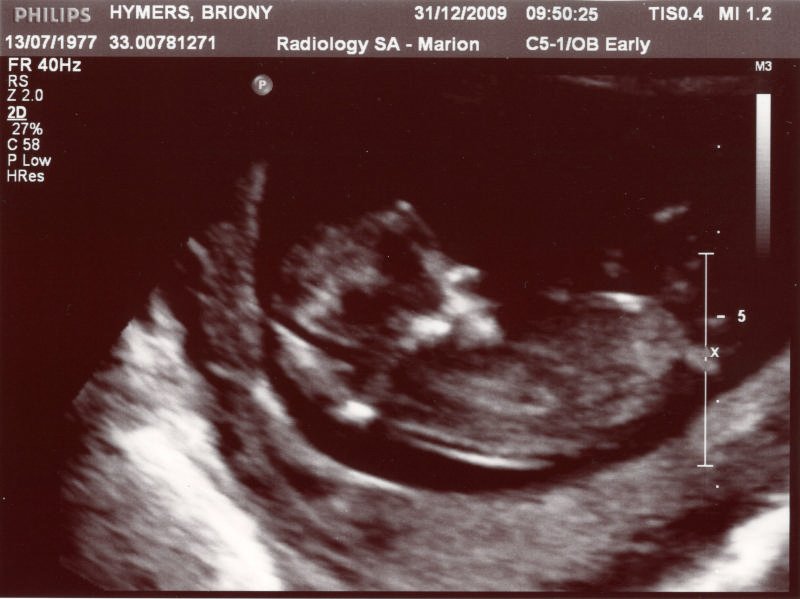

[Week One] Wednesday 7th October 2009 First day of my last period. [Week Two] Friday 16th October 2009 'D' Day [Week Four] Tuesday 3rd November I took a phone call today and after I hung up my eyes blurred over and I was terribly tired for the rest of the day. My stomach is also hurting with premenstral pains and my breasts are sore to touch. It could be a sign of the period coming. [Week Five] Wednesday 4th November I'm two days late. I'm never late. I'm only ever early. I've looked up pregnancy syptoms on the internet - stomach pains, painful stomach, sore breasts, tiredness. Check, check and check! I can't stand waiting anymore so I'm going to get a test tomorrow. [Week Five] Thursday 5th November We walked to the shops after work to get a pregnancy test. I strolled around the shop but couldn't find them, so I had to timidly ask the woman at the counter if they had any. As I was paying for it I made sure that I flashed my wedding ring around just to make sure she didn't think that I was some harlet. On the way home DH decided to tell me that he's going to be earning less at work, nice timing! Now there will possible be three human mouths and a dog to feed on one wage, but he never worries about things like that. That put a damper on my test so I waited a little while until I was over my grump. It soon got the better of me and I took it to the toilet and peed on the stick. We looked together after two minutes.....circle and a cross....pregnant. As I suspected! DH didn't say much (he's as emotionless as Dexter), then the dogs attacked each other, he yelled at them and any portential "moment" was ruined. [Week Five] Friday 6th November Friday is normally gym night where I spend half an hour on a cardio machine and then do half an hour of weights. I knew I wouldn't feel like the cardio so just thought I'd do a few light weights. Jumped on a stepper machine while I waited for DH to finish up. After about two minutes on the lowest setting I felt a horrible pain in my stomach and had to get off. I sat down for five minutes hoping it would settle down. I tried doing arm weights but my stomach was still hurting and I felt horrible so I went home. It hit me on the way home that I now can't do a lot of the things that I used to do. My routine and life were changing. I'll blame it on the hormones, but I had a tearful moment. I think I'm still getting used to the sudden change. [Week Five] Saturday 7th November Before I became pregnant I'd planned a big night out drinking with some friends. However my big night out turned into drinking non-alcoholic punch at dinner while they all got drunk. Then going home at 9pm while they moved onto the pub. Only one of them knew that I was pregnant, so I had to make up excuses why I wasn't drinking [Week Five] Monday 9th November One of my friends told us that there is no point seeing a GP to confirm the pregnancy as they'll just give you a pregnancy test, which I've already done. She said to ring the Hospital of my choice and speak to them. So I had to get DH to ring the Womens Health Clinic at Flinders Medical Centre. I couldn't do it as work would overhear me. So they're sending out some information in the mail and they've given me an appointment for my first midwife visit in early January. We also had to ring a pregnancy help line to get some sort of booking number that the hospital requires. [Week Six] Thursday 12th November Felt fine all day. Took some crackers to work and snacked on them when I felt hungry. Stomach pains started around 2.30pm, different kind of pains. Thought it could be because I had been sitting down and barely moved all day. Felt a bit better when I got home and had dinner. Really tired though and falling asleep at 8.30pm. [Week Six] Sunday 15th November Had to get up at 6.10am today to go sky diving, but didn't feel tired at all. I had a great nights sleep last night. I wasn't sure if I should still go sky diving, but I had paid $400 for it and would have to forfeit the money if I didn't do it. I read up one it and it all seemed fine. After all the baby is only a few cells at the moment. So gliding through the air is not going to damage it. Sky Diving is the most scarey thing I've ever done. I was absolutely terrified when I was sitting outside the plane on the little edge. When my tandem man pushed me forward and we started falling, I had to close my eyes for a few seconds. It was insane! [Week Six] Monday 16th November Feel nearly normal today. My stomach started to hurt a little bit at work after sitting down all day. Didn't feel like eating my dinner, only had a few bites. I felt hungry, but when it came to eating it. I just couldn't. Didn't feel tired today, but now that it's getting to 9pm, I'm getting drowsy. But that's probably because my body is used to going to bed early. It's become routine. My back and shoulders are stiff and sore from sky diving. I think it would be from the sudden jerk when the parachute opened. Eyes are very itchy from hay fever and I'm not allowed to take anything for it. [Week Seven] Wednesday 18th November Went to bed at 8.30pm last night so I woke up at 7.45am this morning. I knew that would be asking for trouble as it meant an extra long day, so at 3pm I had to have a lay down. Was just falling asleep when the neighbours put their noisey as hell reverse cycle airconditioner on....so that ruined that. Geez, it's only 27 today! I read through all the info the hospital sent me and caught up on my Up The Duff book. I have to see a GP about getting a Nuchal Scan done. This is done between 10 and 14 weeks to test for Down Syndrome. I think that the ultrasound may also show up any other defects. It'll also show if there is an Ectopic Pregnancy. You may not even realise it until the scan is done. So I think that its good to have done, just for peace of mind. The hospital doesn't do it, so there is a huge medicare gap. I'll go and see a GP next Wednesday. I also want to get a blood test done now to see if I'm lacking anything from my vegetarian diet. I don't think I would be as I eat better than a lot of meat eaters out there. Meat isn't the cure for everything. [Week Seven] Thursay 19th November I've had the worst stomach pains today. They seem to be high up though, behind my belly button. The pain used to go away after I'd eaten, but that is not helping anymore. I feel hungry but I don't want to eat anything. I thought I was going to be sick at work today, I was very nausious and in a lot of pain. I hope this ends soon. [Week Seven] Friday 20th November I bought tickets to see Mark Seymour at The Norwood months ago. I haven't seen him play for about 6 months, so I didn't want to miss this. Trouble was that I knew he wasn't on stage until 10pm. Seeing my bedtime is now 8.30pm, I knew I'd have trouble staying awake. We arrived at about 9.30 (I somehow mangaged to stay awake) and were lucky enough to get some seats. There was no way that I could stand up for two hours. I started getting bleary eyed half way though he set, but he was awesome as usual and it made it worthwile. [Week Seven] Saturday 21st November. Had a wedding to go to today, lucky for me I didn't have any stomach pains and next to no nausea. The ceremony was at the Botatanic Gardens. The bride was 35 minutes late, and I'd already been there for about 20 minutes before the start time. By the end of the ceremony I was over it and needed to eat. Luckily I had an Up and Go in the car. These things are great to fill you up and get rid of any queeziness. We visted the in laws between the ceremony and reception as we had some time to kill. At the reception I had to drink and toast with orange juice all night, but another guy at our table was doing the same, so I didn't feel too bad. It's a wonder that no one asked why I wasn't drinking. My stomach bloated into a giant ball half way through the evening and it looked like I was already 4 months pregnant. I already had trouble getting my dress on earlier as I think my bust has enlarged!! LOL. So the dress was chaffing at me all night.......a sign of things to come as I'm sure this will get worse. Didn't get home until 1am. I'm sure I'm going to pay for that. [Week Seven] Sunday 22nd November We had to take our foster dog back to the RSPCA. I felt so sorry for her and could barely look at her all morning. Everythime I did I would burst into tears. I cried at the RSPCA when I had to hand her back and cried all the way home! I don't know why I foster, I never handle it very well. We drove to Hahndorf to have lunch with DH's family. I had a disgusting, oily pizza that made my stomach turn. It was lucky that I was feeling fine today, otherwise it wouldn't have sat too well. Not sure why I haven't felt any pain for nausea over the last two days. I hope everything is okay. [Week Nine] Friday 4th December I felt okay today, but my entire stomach is bloated and hard. It looks like I'm 6th months pregnant. I'm having trouble fitting into my jeans and have to undo a button if I sit down. After a bit of research I've found that the bloating is normal and will settle down in a few weeks. Something about the uterous expanding to the size of a grapefruit....joy. Seems like I exchange one sympton for another. Gone is the nasuea, welcome...bloat! [Week Nine] Monday 7th December In the worlds giantest grump today. I'm tired and aching. Just want to go to bed. DH said that I look so fat that I'll have to tell work soon. Seems like my baggy clothes aren't covering the bloated stomach. [Week Ten] Monday 14th December It's week ten this week and to kick it all off I had a huge power chuck this morning. I thought I'd escaped it! I just finished eating raison bread for brekky and started feeling horrible, next thing I'm running to the toilet for three hugh heaves. All I could smell was that disgusting Pregnancy Vitamin that I'd just taken. That's probably what made me sick in the first place, they stink so much that I gag when I take them. So I went to work hungry as I'd just purged my breakfast, I was too scared to eat much in case I had to go running to the toilet while at work....that would be a dead give away that I was pregnant. But I survived without any more episodes. I hope it doesn't happen again tomorrow. I'm huge as ever today. I caught someone looking at my stomach at work today, so I became paranoid and ran to look in the toilet mirror to see if I looked fat. What greeted me was a huge moon faced ogre, and it was so obvious from side on that I'm huge! I need some baggier clothes. [Week Eleven] Sunday 20th December We were invited around for Xmas drinks at the neighbours today, the whole street was there. I wore a dress which nicely covered up my huge stomach. I turned up with my bottle of red creamy soda. It took a few hours before the neighbour asked "Why aren't you drinking wine, you normal drink it?". I mumbled something and someone else joked about it and I thought it was forgotten. But then she said "Is there something you want to tell us?" So of course I had no choice but to confess. Xmas is such a hard time to keep the secret as everyone wonders why I'm not drinking. So now nearly everyone knows except for a few friends and my work. So much for waiting until after the first scan. I hope I don't have to 'untell' them if something is wrong! [Week Twelve] Wednesday 23rd December I'm 11 weeks now, nearly a third of the way through. Had my blood / urine tests done today which included the Downs Test and the general HIV etc etc. Lucky for me there was a place that did them up at Blackwood. So it saved me heaps of time. [Week Thirteen] Thursday 31st December I had my first scan today, Nucal scan. It tests for Down Syndrome and other defects. I'd made my appointment at Radiography SA for 9am. I had to drink a litre of water by 8am as you need to have a full bladder. I didn't finish drinking until about 8.20am, so I hoped I wouldn't get told off. Arrived at 8.45 and they saw me straight away. The doctor lubed me up and placed the 'whatever' it is on my stomach. We were able to see the baby straight away. It had it's arm up in there air like it was waving at us and it then started moving around. I can't believe how much it moved, just like a tadpole! It even spun upside down at one stage. It kinda brings it all home that there is a baby inside me and there's no going back now. You could even see it's heart beating...very cute. The radiographer printed us a lot of photos of the arms, legs etc. I couldn't see to well on the screen as it was angled away from me, but at least I have the prints. The neck fold was about 1mm thick, he said that it's normally only a worry if it's around 3mm, so we should be fine. But the doctors will compare the scan with the blood test for a final decision. Once the radiographer had checked the images while we were in the waiting room, he called us back in as his boss wanted another picture of the nasal bone. Because I'd emptied my bladder and also because the baby was in the wrong position, she had trouble getting a good angle. She was pressing insanely hard on my stomach. She said it's okay for the baby as it's protected, but it just hurts me. When she said "I'm just going to stand up so I can press harder", I knew it was going to hurt. I ended up being there for about 45 mins. It cost $149.50, I'll have to wait and see how much I get back from Medicare. It's 5.93cm long, I'm 12 weeks and two days along and her confirmed that 14th July is the due date. This screening is optional, but I'd definately recommend that everyone gets it done. Not only does it help to pick up any defects, but it's wonderous to see your baby wriggling around like a little worm. We then went to the movies and called in to see my Dad. We didn't get home until very late, and by that time we had to get ready for New Years Eve. Even though I'd been up since 7am, I managed to stay up until 1.30am. I'm so glad that the majority of the tiredness and sickness has passed.

![]()

[Week Thirteen] Sunday 3rd January So much for the nausea ending. I've felt rotten the past two days. I was only commenting to a friend on NYE how I don't feel sick at all anymore. That lasted a whole of two days. [Week Thirteen] Monday 4th January - 13 Weeks It was the first day back at work after having a week and a half off over christmas. I woke up really tired as I went to the cricket last night and didn't get home until late. I ate breakfast and then had my pregnancy vitamin....bad idea! It's definatley what made me spew last time as I felt immediately sick when I had it today and dry reached in the toilet. Luckily I wasn't actually sick. I'm never taking them in the moring again. I got to work and everyone was there, the phones were really quiet so I thought I'd be a good time to tell everyone. I sat down at my bosses desk and said "I"m having a baby". I started shaking from nerves and went all red in the face at being the centre of attention. There was congratulations all round and everyone was excited. A couple of them thought that something was up due to a mystery day off a few weeks ago and the fact that I'd been looking deathly pale. They asked if I was going to resign and I said that I probably will as it's not worth working due to the child care fees. They said to take my marternity leave and see how I go, at least I'll still have the option if I change my mind. It's such a relief that it's out of the way. Now I don't have to wear those extra baggy clothes and pretend to be fit and health. I showed them the scan and one of my work mates says that it looks like Gonzo! That bloody hooter!! I felt sick most of today and I'm really tired. I must be loosing the plot as I forgot to put make up on my chin this morning, looked a bit ridiculos and stood out like a dogs bollocks! Next, Second Trimester or, back to My Pregnancy Site created by Eco Eek! 2009 Some content protected. Other content free for your use. Contact the Webmaster |